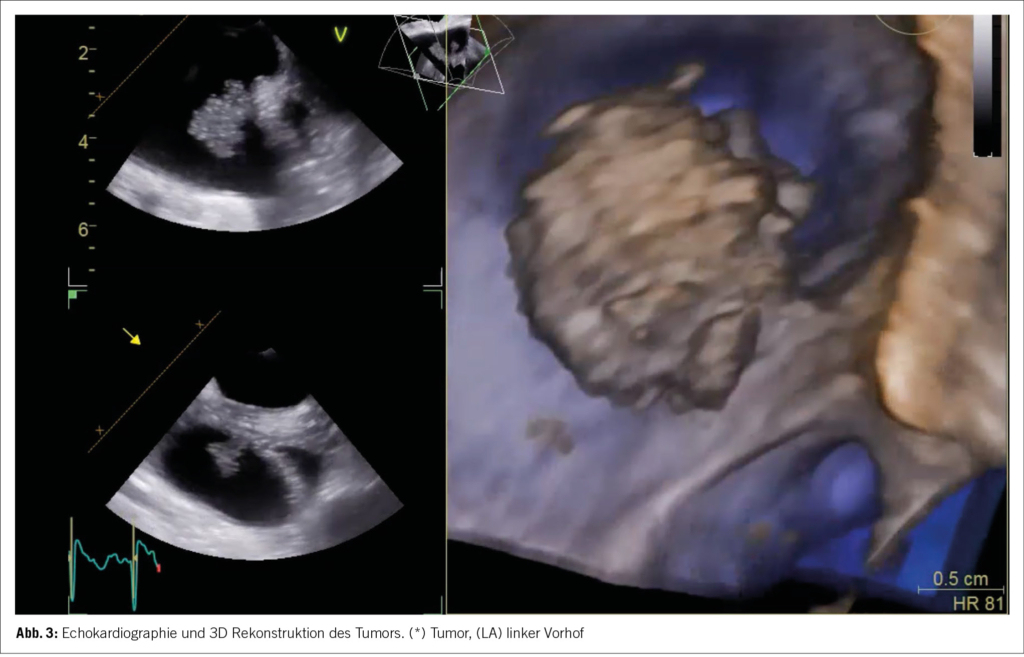

Das Stroke-Work-Up wurde um ein zusätzliches TEE ergänzt. Dieses bestätigte schliesslich den histologischen Befund, mit Darstellung einer 15×18 mm messenden kugeligen flottierenden Struktur zwischen dem linken Vorhof und der linken oberen Lungenvene (im Bereich der Warfarin Ridge, Bild 3). Durch das TEE wurde somit das Herz als primäre Emboliequelle des Hirninfarktes, bestätigt.

Wie bereits in der Fallbeschreibung erwähnt, fiel die erste transthorakale Echokardiographie nach dem Hirninfarkt, unauffällig aus. Nachdem im Thrombusaspirat ein papilläres Fibroelastom gezeigt wurde, erfolgte eine Re-Echokardiographie mittels TEE, wo der Befund bestätigt wurde. Diese Erfahrung steht im Einklang mit Daten der Mayo-Clinic Studie, wo ein zugrundeliegender Herztumor in 70% der transthorakalen Echokardiographien, initial verpasst wurde (13). Deshalb ist es wichtig, insbesondere bei Kryptogenen Strokes, in zweitrangigen diagnostischen Abklärungen, die Bedeutung der transösophagealen Echokardiographie, nicht zu unterschätzen.

Obwohl die Anwesenheit einer Herzneoplasie in der TEE nicht überraschend war, konnte der differentialdiagnostische Verdacht eines Myxoms, aufgrund der Grösse, Lage und Morphologie der Neoplasie im TEE, widerlegt werden. Die unspezifischen klinischen Symptome, wie rezidivierende subfebrile Temperaturen und ein laborchemisch erhöhtes CRP sowie IL-6, unterstützten den echokardiographischen Verdacht der Kardiologen zusätzlich (6).